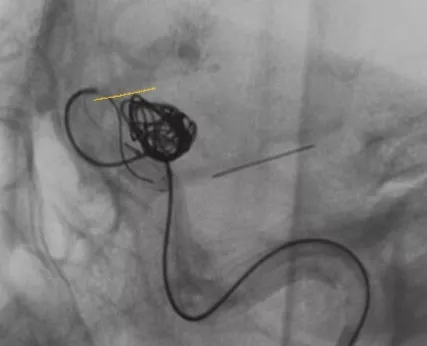

释放支架

找到支架与弹簧圈之间的切线位,继续填塞。支架很好地保护住了颈内动脉和后交通动脉

最后的填塞结果